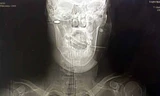

Theo Mirror, con dao đâm sâu khoảng 10mm vào đầu nạn nhân, khiến anh phải mất 2 tuần điều trị trong bệnh viện.

Các bác sỹ cho biết, vết đâm chỉ sâu thêm một chút là nạn nhân có thể bị nguy hiểm tới tính mạng.